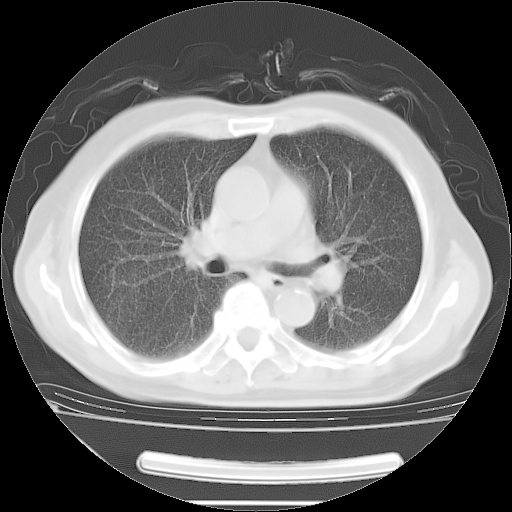

今天复查肺部CT,发现双肺广泛磨玻璃样改变。所以我把3月19日和5月9日相隔50天的肺部CT上传。请大家会诊。

5月9日肺部CT(在4月27日齐鲁医院肺部CT描述部分肺组织磨玻璃样改变,12天后肺组织广泛磨玻璃样改变)

2009年5月9日肺部CT

大致读了系列胸部CT:纵隔窗无明显异常,肺窗:从4、27至今:主要是双肺中下野外带可见毛玻璃样改变,目前处于急性肺泡炎阶段,至于原因考虑1、结替组织或胶原血管性疾病所致?2、恶性疾病如恶组在肺部所致的表现或细支气管肺泡癌?3、药物或其它原因如肺蛋白沉着症所致肺泡炎目前不太可能?总之,明天就去请我院的呼吸科、感染科、血液科和临免专家会诊哈。